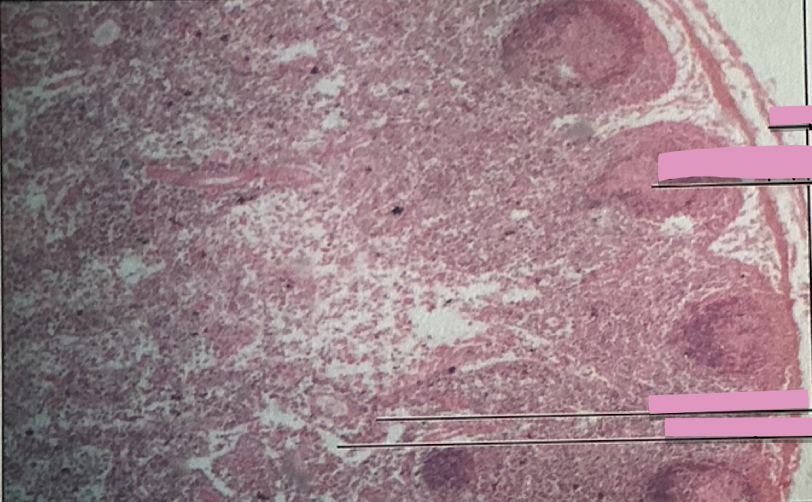

lymph node

each lymph follicle w/in each lymph node is active center for ___________

______________ capture antigens and bring them to lymph nodes